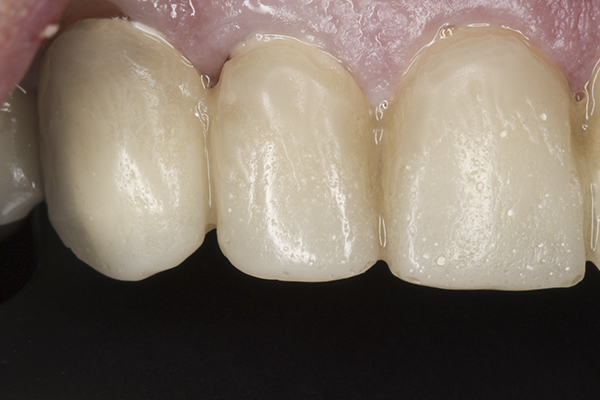

(38.) Postoperative right anterior, close-up view.

Figure 38

(39.) Postoperative anterior, close-up view.

Figure 39